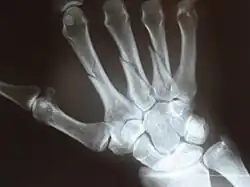

X-ray

X-ray image of right hand with thumb on left.

Multiple fractures of the metacarpals (aka broken hand). (Right hand shown with thumb on left.)